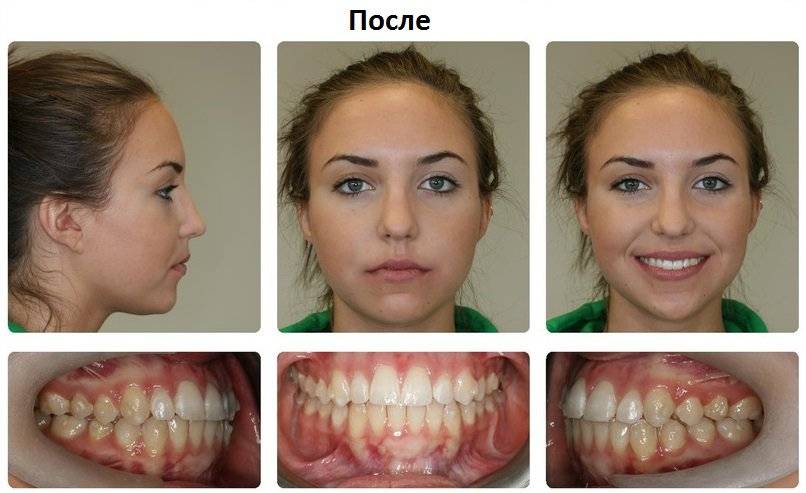

Фотографии и схемы для ОПТГ и мезиального прикуса